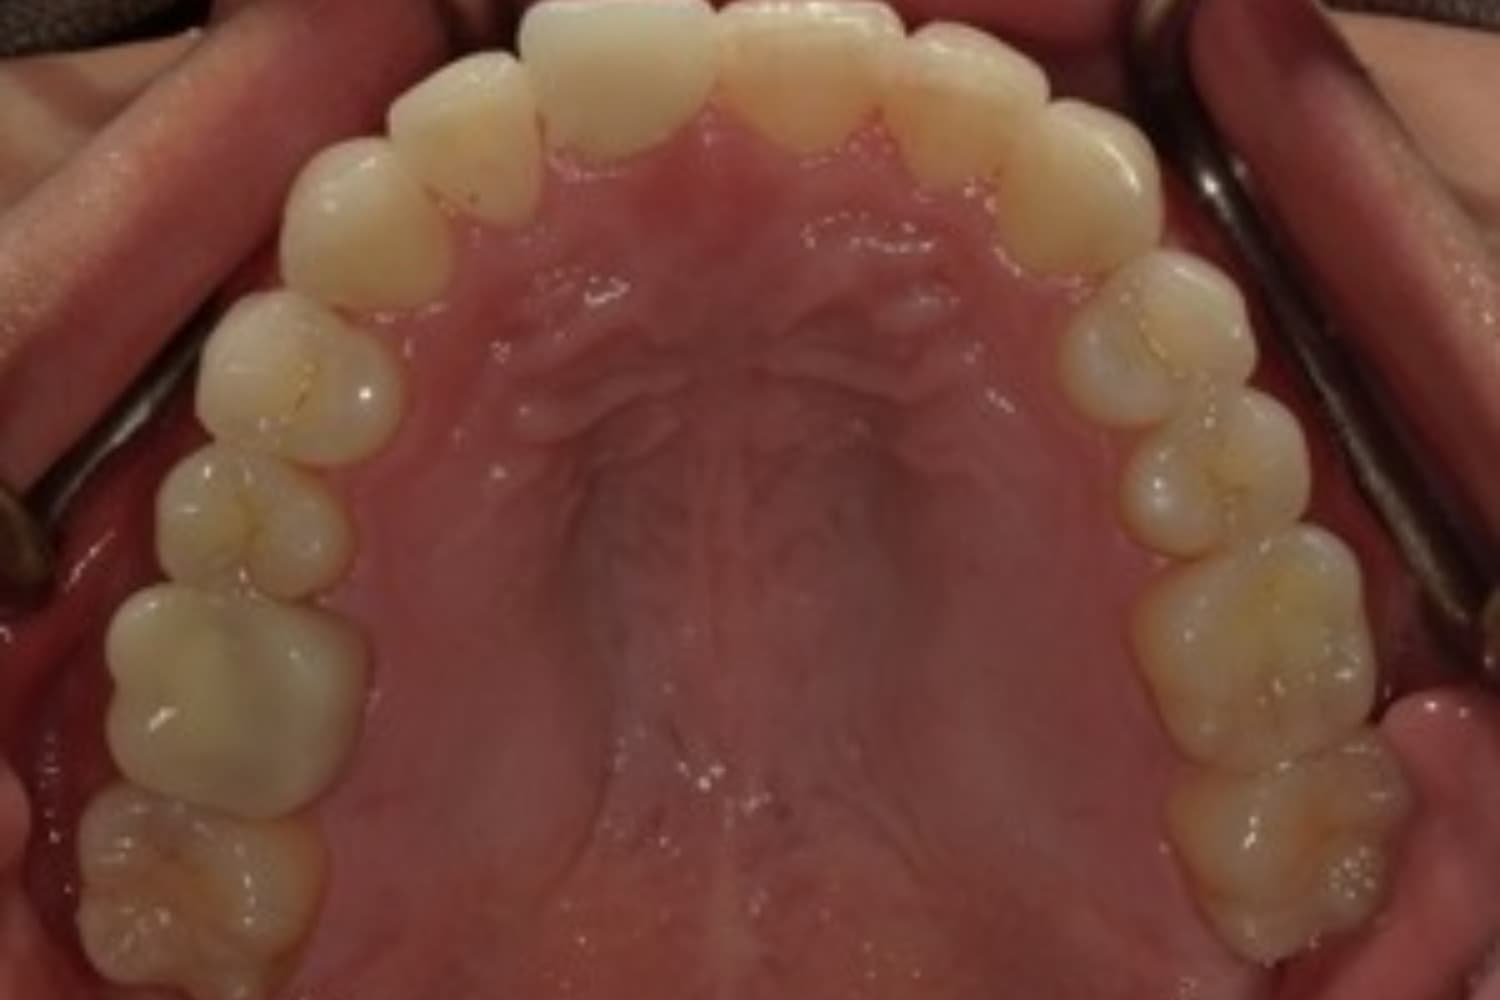

ガタガタとした歯並びや八重歯(1)

Before

After

ガタガタとした歯並びや八重歯をマウスピース矯正(インビザライン)にて治療

主訴

下の前歯のガタガタが気になる

治療期間

2年5カ月

費用

90万円

副作用・リスク

・矯正治療による歯の動きには個人差があり、想定より治療期間が延びることがあります。 ・矯正治療で歯を動かす際に痛みをともなうことがあります。 ・指示された通りに保定装置を装着しないと、歯並びや噛み合わせの後戻りを引き起こす可能性があります。